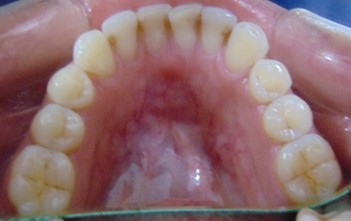

Divya Patil, 28Y, Duration - 6Months

Before

After

Image 2